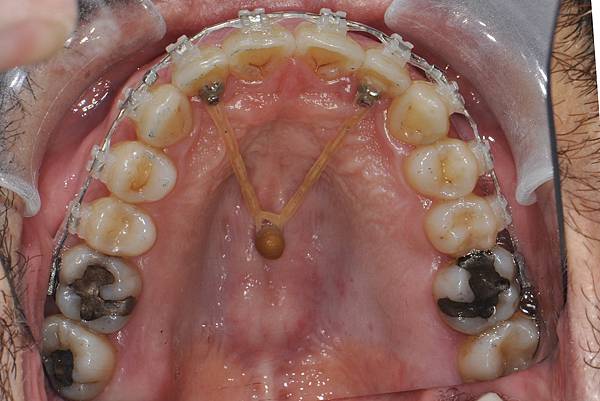

台灣的牙科醫療品質, 連外國人都說讚!此案例為深咬合併二級咬合 林醫師藉由正中上顎骨釘(HPPG technique)做上顎全齒列後移改善暴牙 讓本來五官就相當立體的艾先生,笑起來更燦爛了! 治療前/治療後-以上案例由林昇進醫師提供 分享到